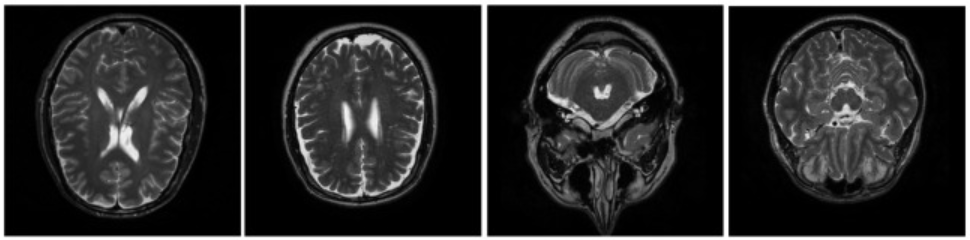

Magnetic resonance imaging (MRI) has transformed medical imaging. This non-invasive test produces high-quality images of the body's internal structures without using harmful ionising radiation1. Today, MRIs are the preferred method for diagnostic imaging of soft tissue structures like the brain, spinal cord, musculoskeletal system, small bones, liver, and pelvic area2. They can also detect abnormalities in vascular structures such as blood vessels3.

MRI scans produce detailed images of the body’s internal structures, such as organs and tissue. They produce these images by using the magnetic properties of hydrogen atoms, which are found throughout your body due to their abundance in water and fat4. When your body is in an MRI scanner, strong magnetic fields cause the hydrogen atoms to act as tiny magnets, and they all align with the magnetic field. Radio waves are used in short bursts to knock the hydrogen atoms out of their magnet-induced alignments. When the radio waves are turned off, the hydrogen atoms realign with the magnetic field, releasing a signal. This signal is detected by the scanner and used to create the image of the body4.

An increase in magnetic field strength increases the signal received from the body. This increases the signal-to-noise ratio, providing an image with higher quality7. This may allow health professionals to more effectively assess the presence of abnormalities in the image and improve diagnostic confidence8.